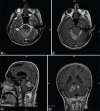

Intravascular papillary endothelial hyperplasia (IPEH) also known as Masson's tumor, is a benign, slow growing, vascular lesion which is seen very rarely and only a few cases have been reported intracranially in the literature. It has been reported at many sites, but the posterior fossa involvement is very rare. The preoperative diagnosis is very difficult, as there is no enough cases to achieve a clear understanding about the details of its radiological findings. Differential diagnosis have to be made especially from angiosarcoma and meningioma. It is curable by total surgical removal. In this article we presented the characteristic clinical, radiological, perioperative and pathological findings in a case of IPEH in an unusual location, origin and behavior. To best of our knowledge, we presented the first case of IPEH originating from tentorium.